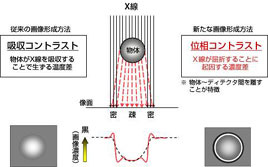

fig3 位相イメージングの原理

X線が物体を透過するとX線画像が形成されることはすでに述べましたが、(Fig.3)。これは吸収コントラストと呼ばれています。一方、X線そのものは可視光同様に電磁波なので、物体を透過するとX線の位相が変化。この位相変化が、一般に屈折や干渉として観測されます。この位相変化に基づくX線強度差あるいは画像コントラストが位相コントラストであり、吸収コントラスト+位相コントラストの組み合わせが高画質化のキーとなっています。

X線撮影における位相コントラスト技術は、人体(被写体)を透過した直後のX線そのものの画像をエッジ強調効果により、シャープさ(鮮鋭性)を向上させるもので記録側の画質向上を行ってきた、従来からのアプローチとは全くちがう革新的なものとなっています。